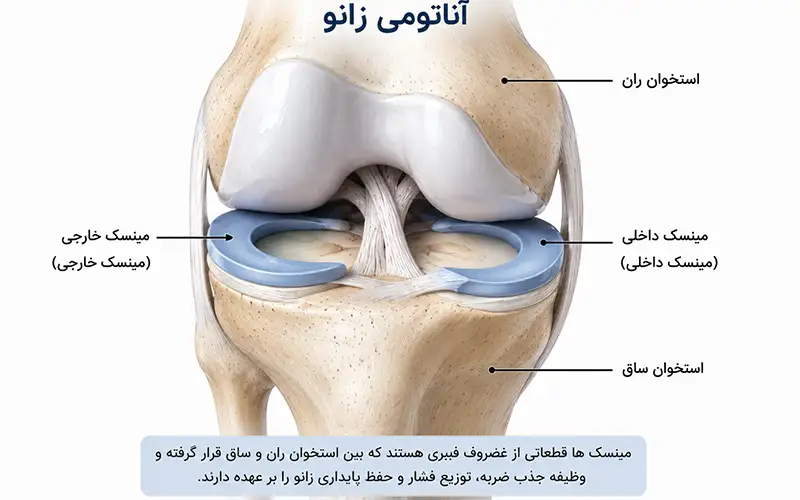

آیا منیسکهای زانو عروق و اعصاب دارند؟

منیسکهای زانو از نظر خونرسانی به سه ناحیه اصلی تقسیم میشوند: ناحیه قرمز (Red Zone)، قرمز–سفید (Red-White Zone) و سفید (White Zone) که از حاشیه به سمت مرکز منیسک قرار دارند.

بهجز بخش محیطی منیسکها، سایر قسمتها فاقد عروق خونی هستند و تغذیه آنها از طریق انتشار مواد غذایی از مایع مفصلی انجام میشود. حدود ۱۰ تا ۳۰ درصد از حاشیه خارجی منیسک خارجی و ۱۰ تا ۲۵ درصد از حاشیه منیسک داخلی دارای عروق خونی هستند.

اعصاب منیسکها مسیر عروق را دنبال میکنند و بیشترین تراکم عصبی در نواحی شاخ قدامی و شاخ خلفی منیسکها دیده میشود که نقش مهمی در حس عمقی و درد زانو دارند.

منیسک یکی از مهمترین ساختارهای محافظتی مفصل زانو است که نقش اساسی در جذب ضربات، حفظ ثبات ...

ویژگیهای منیسک داخلی زانو

منیسک داخلی زانو ساختاری به شکل حرف C باز دارد و شعاع انحنای آن از منیسک خارجی بیشتر است. ...